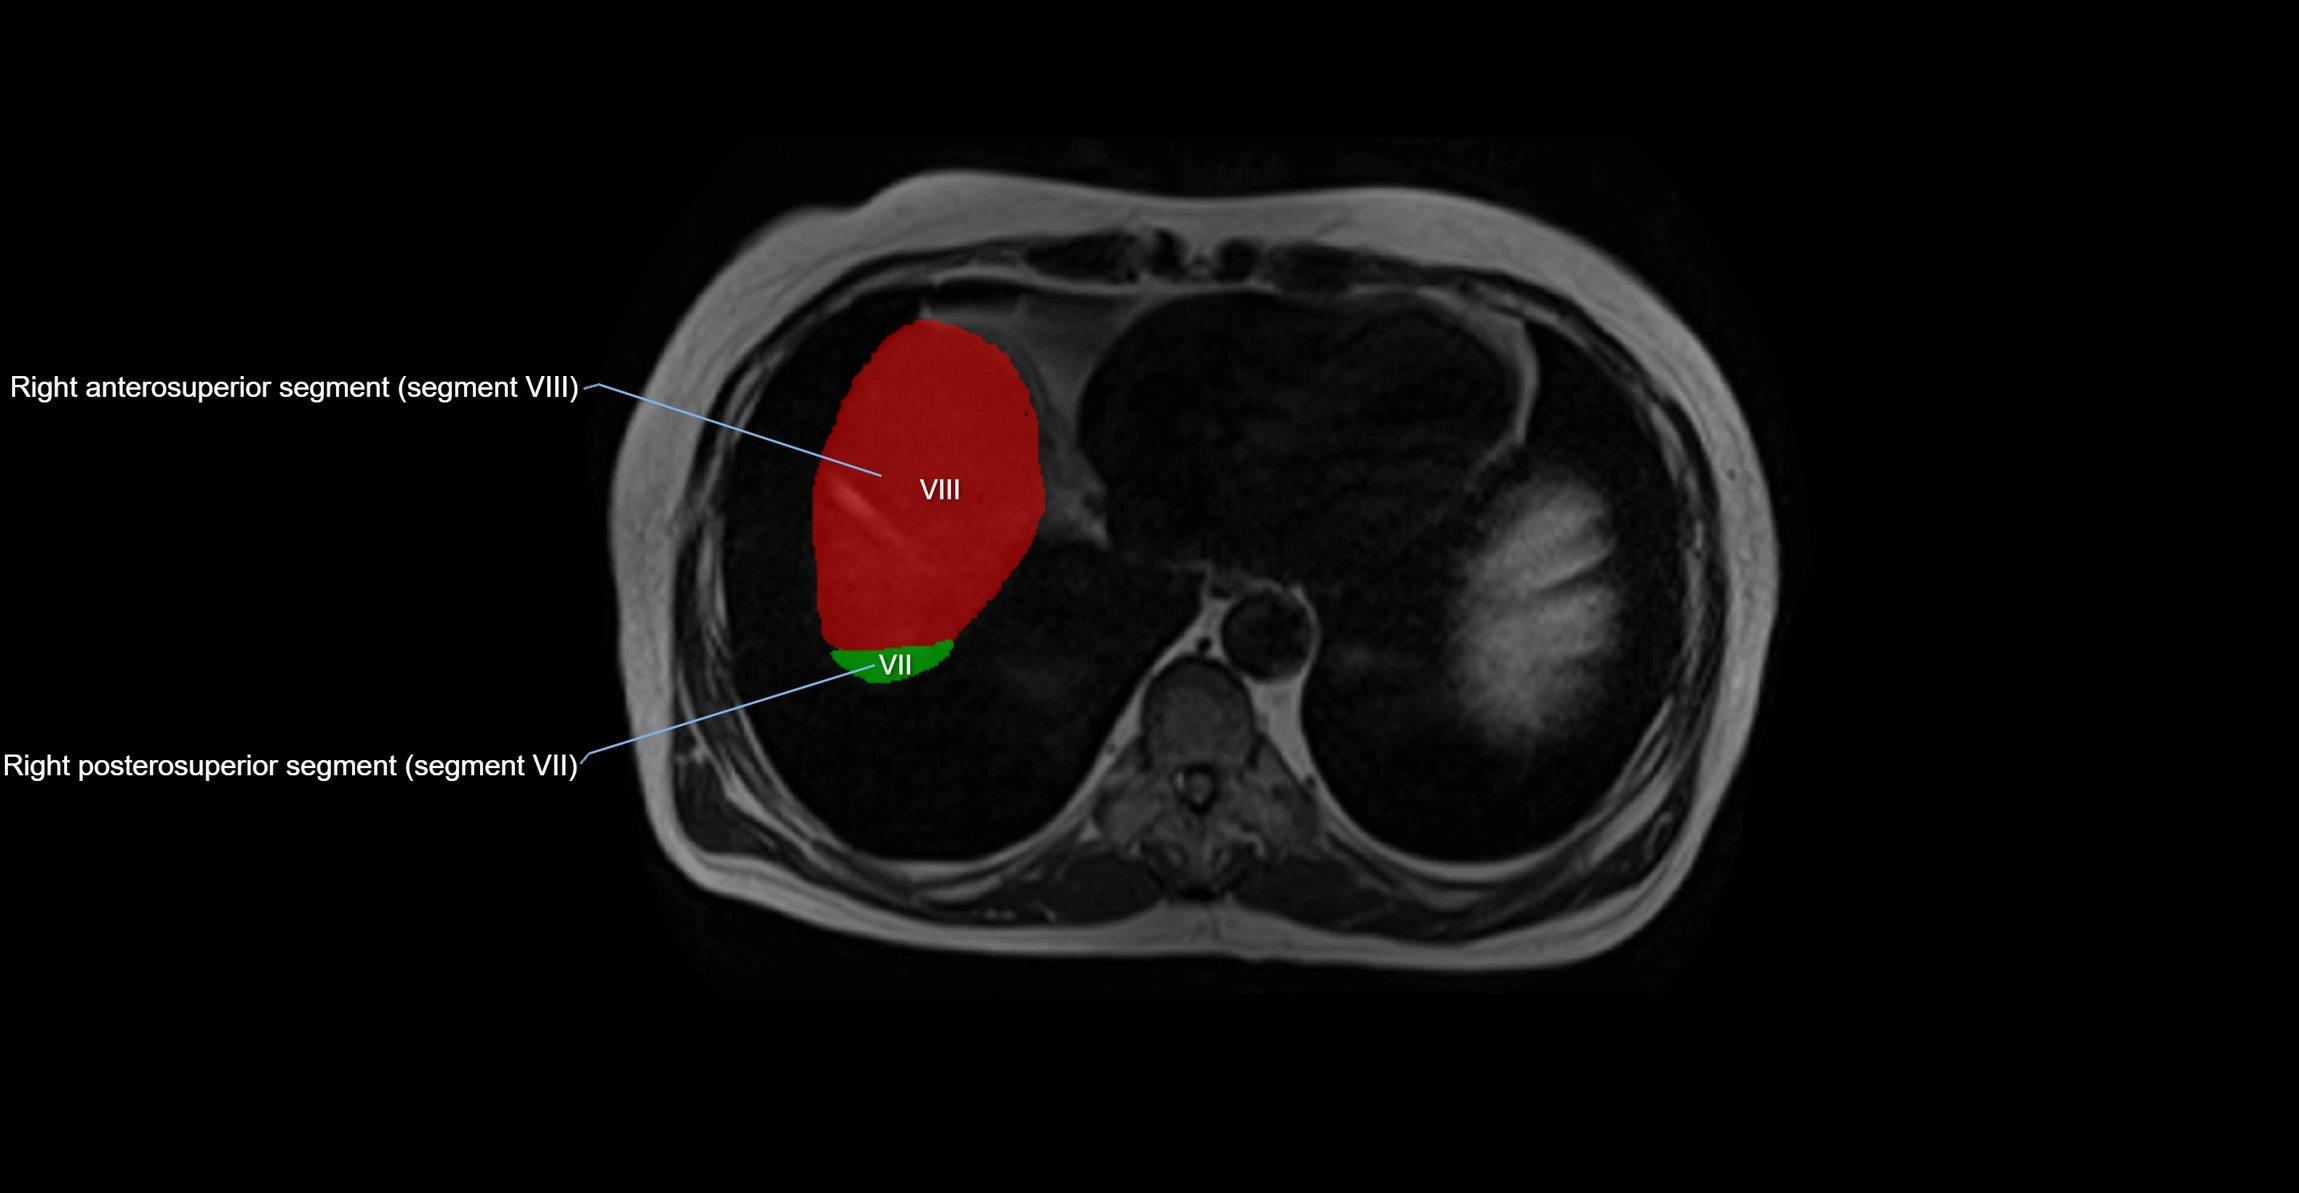

MRI image

image